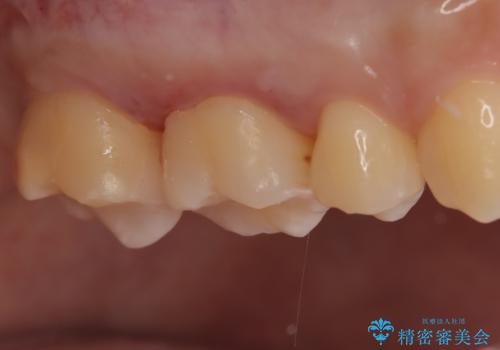

- 金属を外してセラミックを入れたいことを主訴に来院された患者さんです。

セラミックインレーにて修復を行いました。